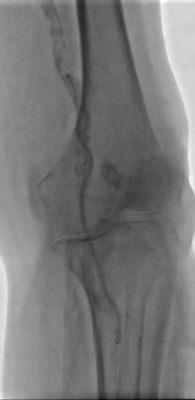

1. 术前造影:

2. 经鞘置入椎管、CXI、V18导丝正向开通股浅动脉下段,导丝通过,导管无法跟进,经皮穿刺钙化灶,导管跟进造影发现位于内膜下。